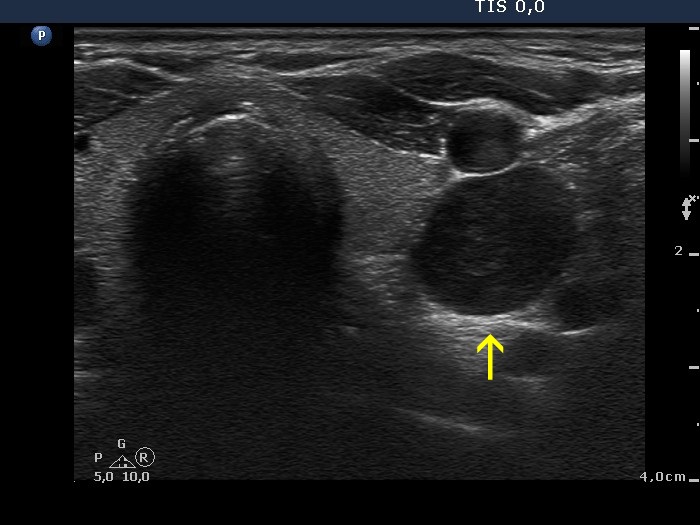

Parathyroid adenoma (histology) - case 671 |

Transverse scan |

Longitudinal scan |

This is a deeply hypoechoic lesion which proved to be a parathyroid adenoma (yellow arrow). The longitudinal images prove that the adenoma was located upper to the thyroid (red arrows). Parathyroid adenomas are almost always hypoechoic.